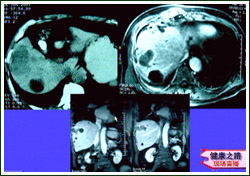

主持人:来看一味患者的情况:这位老先生去年六月份被确诊为肝癌,当时的肿瘤大小是七乘九厘米,由于肿瘤的位置不当,加上老人有自己的想法,没有采取手术切除的方法。去年7月13日老人接受了导管栓塞化疗,但术后的感觉不是太好,大约有一周的时间不想吃饭、坐不起来、一点劲也没有,老人觉得这种方法对他也不是太合适,如果再做,肯定受不了。在这种情况下,老人又听说了微波治疗的方法,于是去年9月18日老人做了第一次治疗。患者:"当时做的时候有一点疼,但还是可以忍受,因为温度毕竟不是很高而且时间短,创伤也非常小,手术当天下午在床上躺了半个小时侯就可以下床了,也可以自己去上厕所了,感觉身上不象以前那样难受了,活动基本正常,第二天就可以吃饭了。" 何文:来看这位患者的片子:在肝右部有一个9厘米的肝癌,治疗后肿瘤明显缩小,形成的薄膜可以限制肿瘤的扩散和转移,治疗后肿瘤区完全坏死,患者治疗后已经存活一年多了,正在随访过程中。

主持人:来看另外一位患者的情况:这位患者是突然肝癌破裂后到医院进行抢救,接受了微波治疗。患者:"去年6月14日我在家里拿花盆时觉得筋拽着脖颈,一直到肩膀,筋拽着疼,送到密云县医院后观察了四、五个小时,由于肝癌破裂大出血,流了6000多毫升血,经过输血抢救后在医院住了15天,以后做了微波治疗后感觉精神好多了,比较重的体力活儿完全可以干,胃口也很好。" 何文:我们来看看对这位患者进行微波治疗的情况:如图肝脏的右叶有一个五乘六厘米的肝癌,治疗后肿瘤明显缩小,肿瘤区完全坏死,患者治疗后的各项指标都恢复了正常,说明对于这一类患者微波凝固治疗也是有效的。 董宝玮:微波局部热疗的优点是在造成肿块本身局部坏死的同时可以激活机体的抗肿瘤免疫功能,因此治疗效果是不错的。